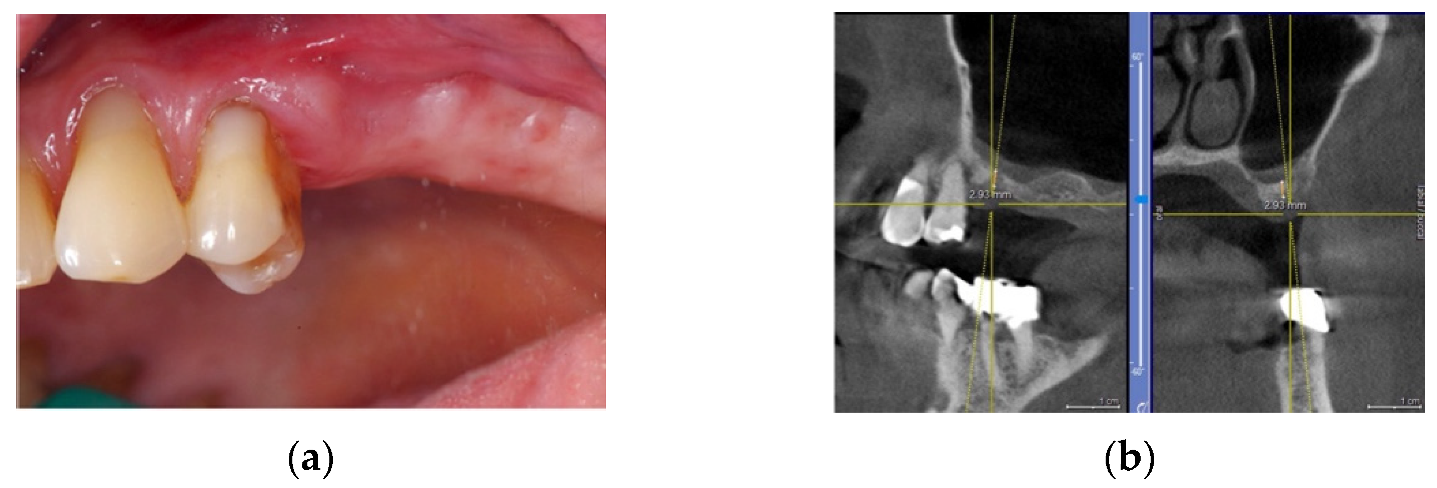

4.1. Clinical Case n.1.

4.2. Clinical Case n.2.